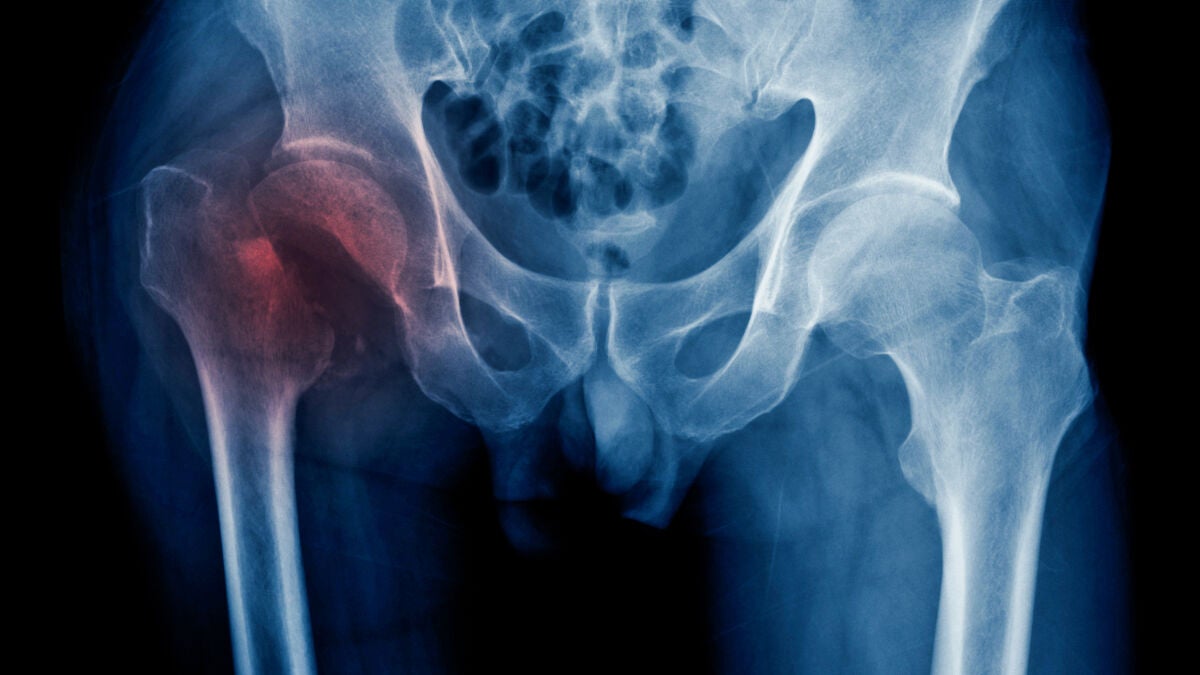

Las fracturas de cadera tienen más riesgo de desencadenar eventos cardiovasculares adversos

Un estudio ha hallado que la insuficiencia cardíaca o el infarto de miocardio tienen un mayor riesgo de aparecer tras una fractura de cadera. Este descubrimiento puede facilitar la introducción de tratamientos personalizados para los pacientes con fractura de cadera.

Un equipo de investigación del Departamento de Farmacología y Farmacia de la Facultad de Medicina de Hong Kong (China) ha descubierto que las fracturas de cadera pueden desencadenar eventos cardiovasculares adversos, y que aquellos pacientes con afecciones cardíacas preexistentes tienen cinco veces más riesgo de sufrir este tipo de eventos, lo que se traduce en un peor pronóstico y un mayor uso de los servicios sanitarios.

El estudio, publicado en la revista Nature Communications, muestra que eventos como la insuficiencia cardíaca o el infarto de miocardio tienen un mayor riesgo de aparecer tras una fractura de cadera, y en el que los científicos han registrado "una notable falta de énfasis" en su manejo.

Los investigadores han usado el Big Data y la IA para descubrir características clínicas ocultas de pacientes con fractura de cadera de diferentes etnias, basándose en los registros sanitarios electrónicos de Hong Kong y Reino Unido de más de 100.000 pacientes con fractura de cadera, cuya mortalidad en la ciudad es aproximadamente del 17 por ciento, superior a la de pacientes con cáncer de mama, tiroides y próstata.

Además, han descubierto que el grupo de pacientes relativamente sanos (66 por ciento) exhibía un menor riesgo de sufrir eventos cardiovasculares, en comparación con aquellos con enfermedades relacionadas con el metabolismo (21,4 por ciento) y aquellos con antecedentes de insuficiencia cardíaca congestiva o arritmia (12,6 por ciento).

De hecho, el grupo de personas con enfermedades metabólicas tiene el doble de riesgo de hospitalización por este tipo de eventos en los 180 días posteriores a la fractura, y el grupo con antecedentes ha presentado un riesgo cinco veces mayor de hospitalización en el mismo periodo y por la misma causa.

El equipo de investigación también ha encontrado un riesgo "significativamente elevado" de eventos adversos cardiovasculares dentro de los 60 días posteriores a la fractura, lo que sugiere que esta podría contribuir por sí misma a un mayor riesgo a corto plazo de este tipo de eventos. Este riesgo acaba disminuyendo en el periodo de entre 61 y 180 días, unos datos similares a los del grupo analizado de Reino Unido.

"La calcificación vascular es un factor de riesgo conocido de eventos cardiovasculares. Los huesos sirven como un depósito vital de calcio en el cuerpo; el aumento repentino del calcio en sangre después de las fracturas puede aumentar el riesgo de accidente cerebrovascular y enfermedad cardiovascular. Por lo tanto, es muy importante gestionar rápidamente el riesgo de eventos cardiovasculares después de una fractura de cadera", ha añadido Cheung.